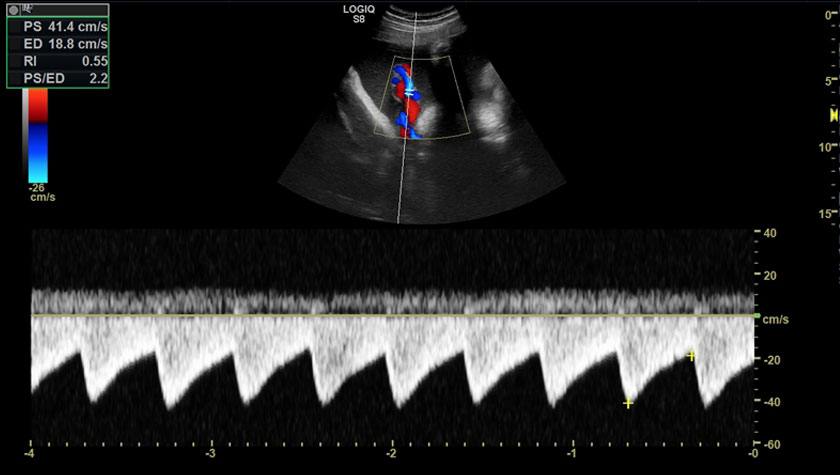

Для УЗИ сосудов врачам необходимы технологии, обеспечивающие высокую проникающую и разрешающую способности.

- Инновационные датчики XDclear и технологии – обеспечивают впечатляющую глубину проникновения и чувствительность даже у пациентов с избыточной массой тела. Система также обладает высокой разрешающей способностью и чувствительностью к кровотоку в мелких поверхностных и глубоколежащих сосудах.

- Режим B-flow – оценивает гемодинамику во всех типах сосудов: от крупных кровеносных сосудов, например, сонной артерии, до мелких сосудов паренхиматозных органов.

- CD — цветное допплеровское картирование

- PW — импульсно-волновой спектральный допплер

Аортальный клапан, режим цветного доплера, датчик M%S-D